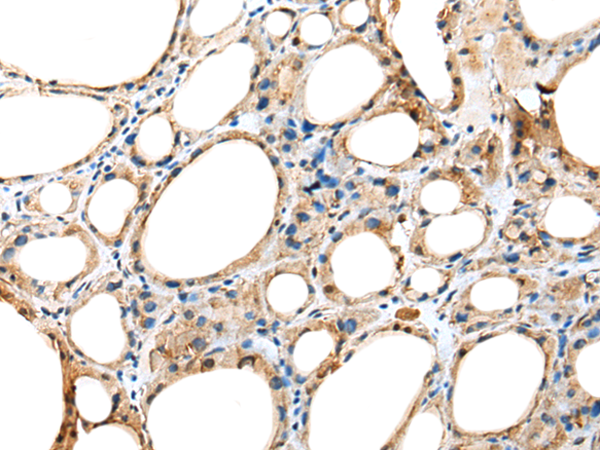

分类: 科研抗体货号: P02313别名: NA88A; HPX42B; VENTX2应用: IHC反应种属: Human